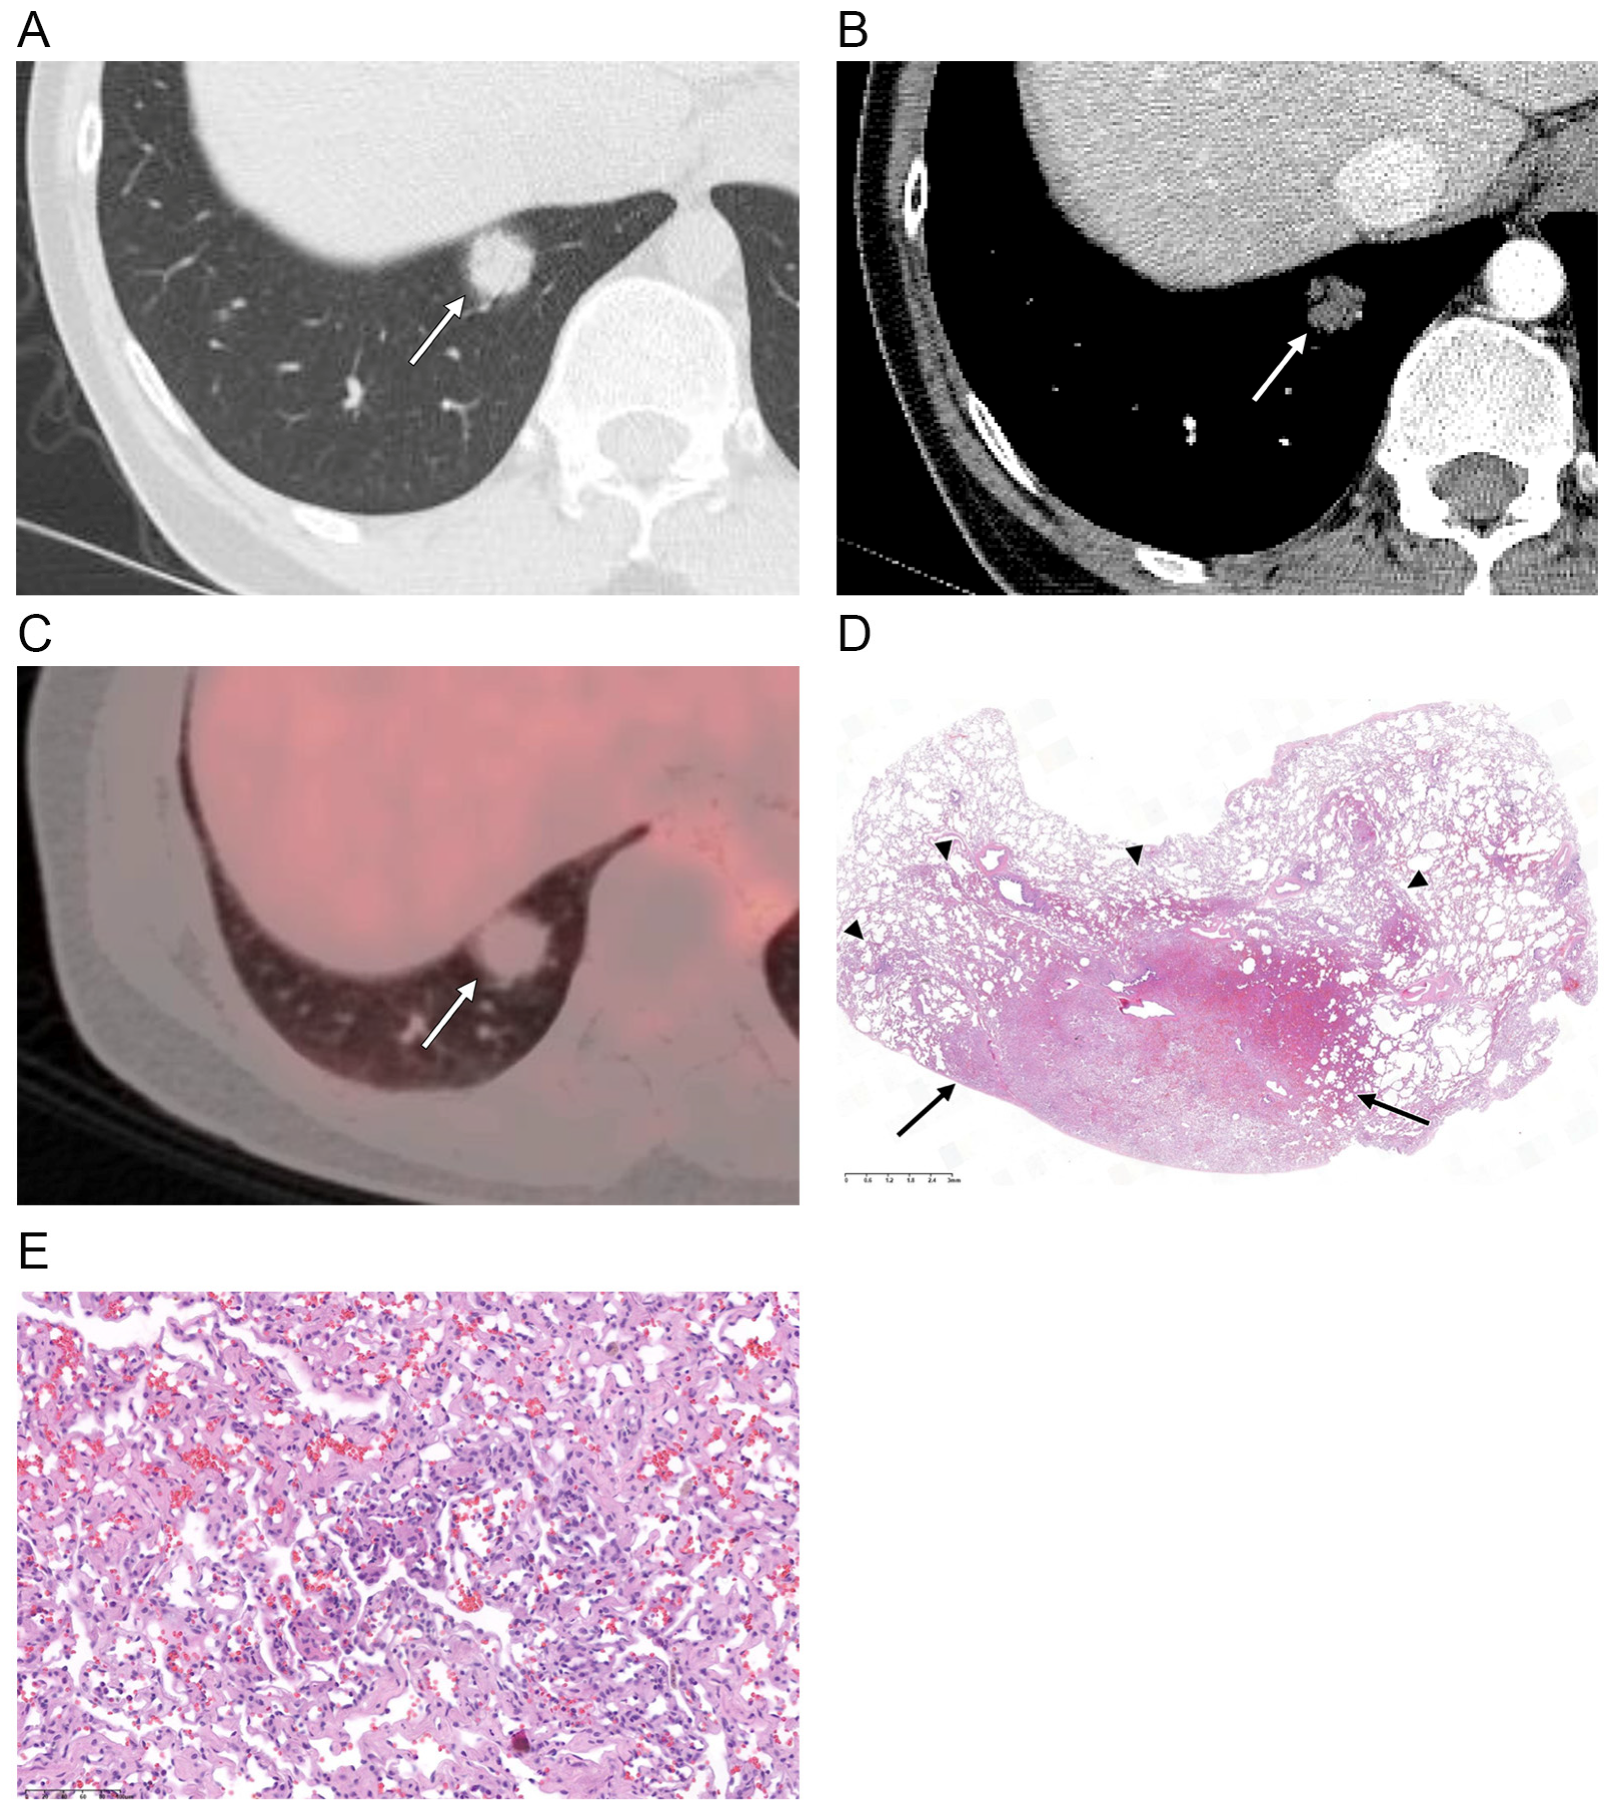

| Nodule density | |

| Ground-glass | 1 (6) |

| Part-solid | 15 (88) |

| Solid | 1 (6) |

| Lobe | |

| RUL/RML/RLL | 1 (6)/1 (6)/8 (48) |

| LUL/LLL | 2 (12)/5 (30) |

| Location | |

| Central | 2 (12) |

| Peripheral | 15 (88) |

| Contour | |

| Smooth | 16 (94) |

| Lobulated | 1 (6) |

| Margin | |

| Well-defined | 8 (47) |

| Ill-defined | 9 (53) |

| Perivascular lucency | 2 (12) |

| Air bronchogram | 10 (59) |

| Pleural retraction * | 0 (0) |

| Enhancement ** | |

| Hypoattenuation | 14 (93) |

| Isoattenuation | 1 (7) |

| FDG uptake on PET-CT † | |

| Hypometabolic | 10 (100) |